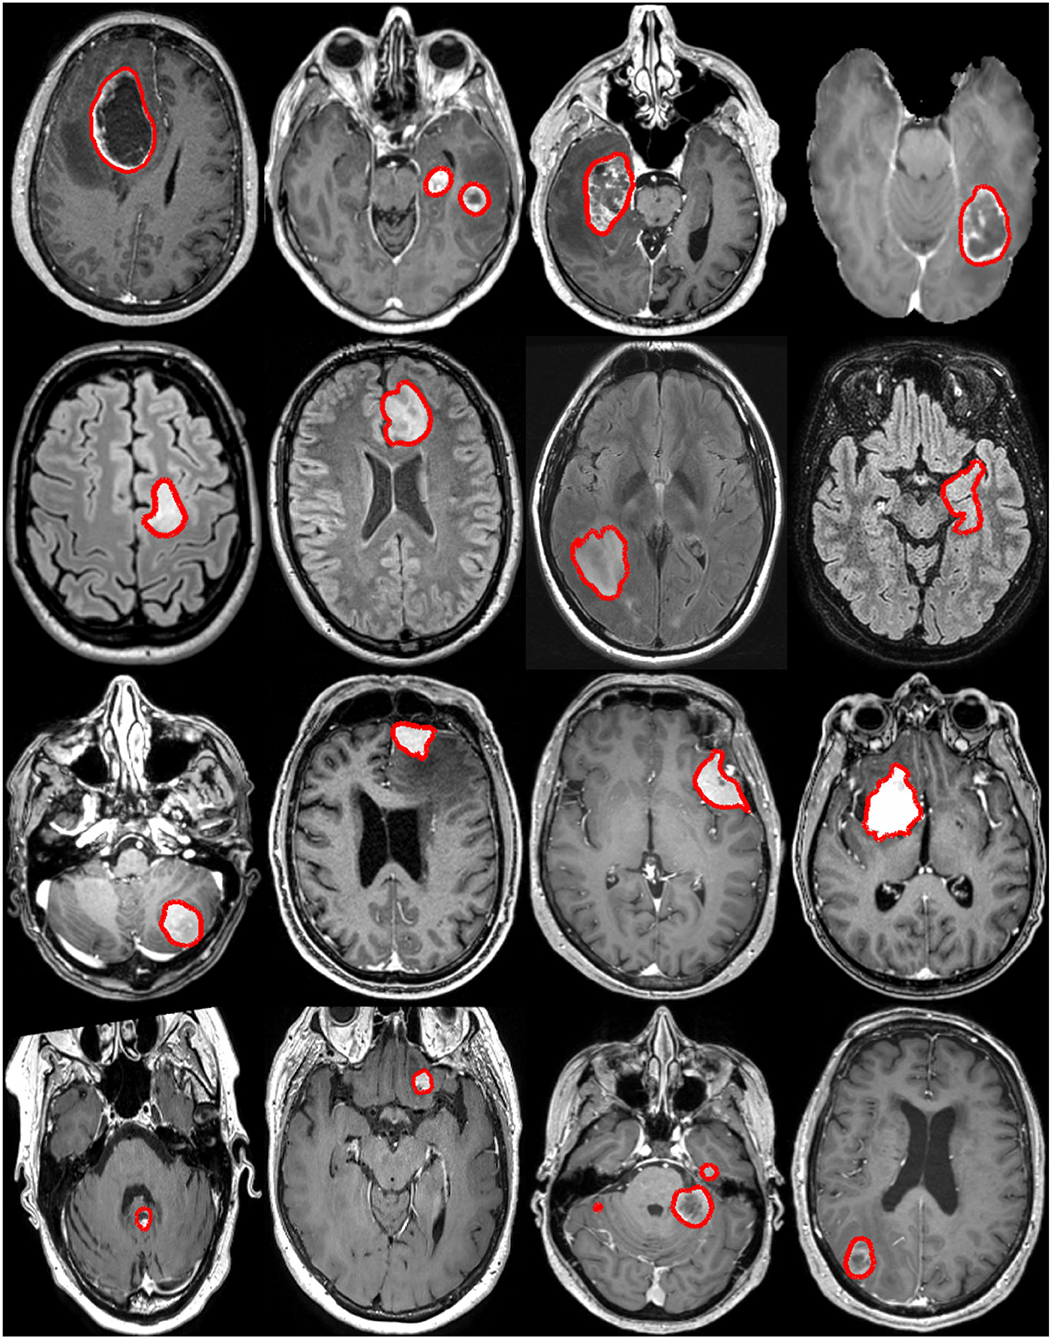

Perhitungan Volume Tumor Otak Menggunakan Metode Active Contour Pada Modalitas MRI

Kanker otak adalah kondisi medis yang serius yang memerlukan perawatan yang cermat. Salah satu langkah penting dalam manajemen kanker otak adalah dengan mengukur volume tumor secara akurat. Citra Magnetic Resonance Imaging (MRI) adalah salah satu alat diagnostik yang paling penting dalam bidang medis yang digunakan untuk visualisasi otak. Dalam artikel ini, akan dijelaskan bagaimana metode Active Contour dapat digunakan untuk menghitung volume tumor otak pada citra MRI dan bagaimana visualisasi 3D dapat membantu dokter dalam diagnosis dan perawatan yang lebih baik.